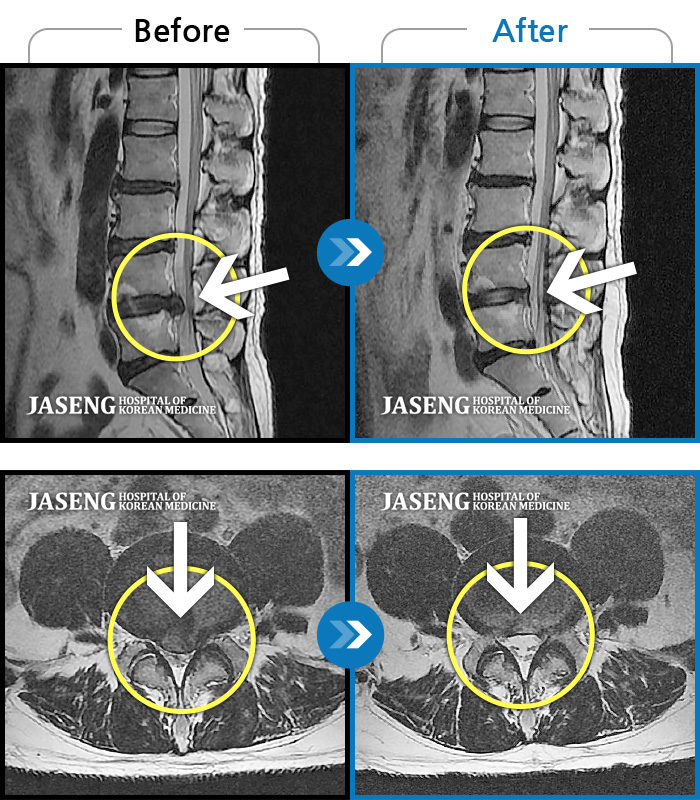

허리디스크

도움받은 사례

일산 · 김진수 원장

처음 내원 시 좌측 엉덩이가 많이 아프고, 좌측 다리로 저림이 심하며 특히 좌위시 하지 방사통이 심하여 1분도 좌위가 어려워 식사도 서서 하는 등 정상적인 활동이 힘든 상태였습니다.

촬영시기

2021.11.12 ~ 2024.07.23

2024.11.08

조회수 587